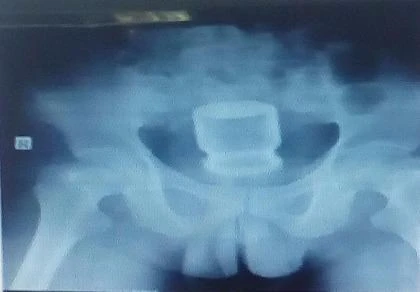

Vị trí lọ nước yến còn nguyên nắp trong cơ thể bệnh nhân. Ảnh: PLO.VN

Kết quả nội soi trực tràng và X-quang cho thấy lọ thủy tinh còn nguyên nắp đậy, bên trong chứa đầy nước yến. Do không thể nội soi để lấy lọ nước yến ra khỏi cơ thể anh L. nên các BS phải phẫu thuật cấp cứu.